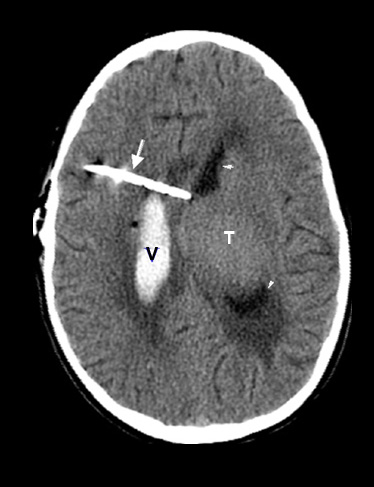

Case 7:

Thalamic tumor, resulted in marked degree of hydrocephalus requiring shunt catheter placement. Hemorrhage followed placement of the shunt.

Figure 7: Pre-contrast axial CT findings of shunt induced intraventricular hemorrhage:

- T: Thalamic tumor

- Arrow points to the shunt

catheter

- V: Intraventricular blood

- Arrowheads point to normal CSF within the left lateral ventricle